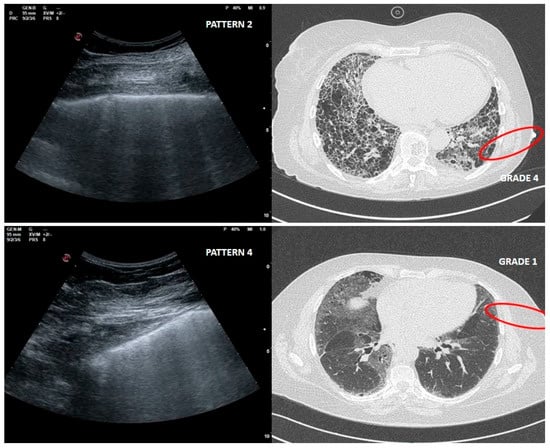

Four echographic patterns were described corresponding to worsening fibrotic changes of the peripheral lung: (1) normal or near normal; (2) SIS with predominance of reverberant horizontal artifacts; (3) SIS with vertical predominance and altered pleural line; (4) white lung with altered pleural line (Figure 1).

Figure 1. LUS patterns. (A): pattern 1, near normal; (B): pattern 2, SIS with predominance of reverberant artifacts; (C): pattern 3, SIS with vertical predominance and altered pleural line; (D): pattern 4, white lung with altered pleural line.

As far as LUS pattern 2 is concerned, agreement with HRCT grade 2 has been reported in 24 out of 30 cases (77%). It is really important to focus on the 4 cases in which a LUS pattern 2 was associated with HRCT grade 4 related to peripheral large honeycomb cysts (massive fibrosis subversion) (Figure 3).

Figure 3. Upper right and left: large cysts honeycombing and severe fibrotic changes (red circle) with corresponding LUS pattern 2. Bottom right and left: ground glass opacities and moderate fibrotic alterations (red circle) with corresponding LUS pattern 4.

Large cysts honeycomb could represent a limit for LUS, as in this case the air content is greater than in a healthy condition [24].

This misleading case, in which fibrotic changes were moderate but ground glass opacity (GGO) was reported, corresponded to an early phase of acute exacerbation of IPF (Figure 3).